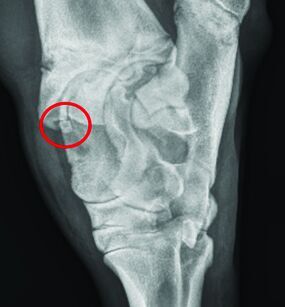

These images were taken recently of a yearling bull that presented for significant hock swelling and grade 3/5 left hind lameness. The circles show a common location of an OCD at the medial malleolus. Images shared with owner permission. Thank you!